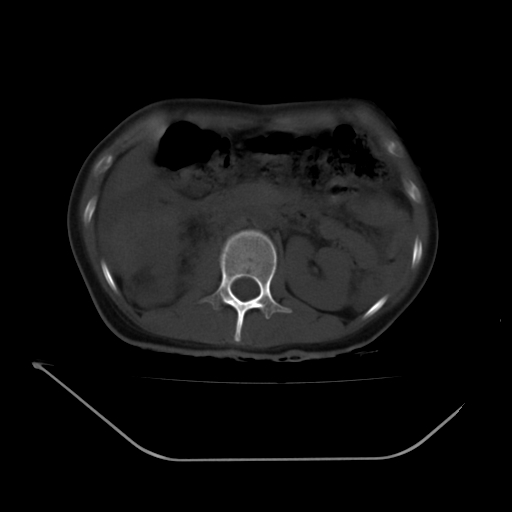

以下是引用liuyue在2008-7-19 13:02:00的发言:[br]1.肝右叶后下段及右肾挫裂伤伴腹腔积血。[br]2.右侧多发性肋骨骨折、横突骨折、右髂骨骨折伴周围软组织挫伤。[br]3.右侧腰大肌肿胀,并可见低密度影,如为气体,则肠道挫裂伤待除外。

以下是引用zhengfaming在2008-7-19 14:42:00的发言:[br]1.肝右叶后下段及右肾挫裂伤伴腹腔积血。脾脏挫裂伤待排[br]2.右侧多发性肋骨骨折、横突骨折、右髂骨骨折伴周围软组织挫伤。[br]3.右侧腰大肌肿胀,并可见低密度影,如为气体,则肠道挫裂伤待除外